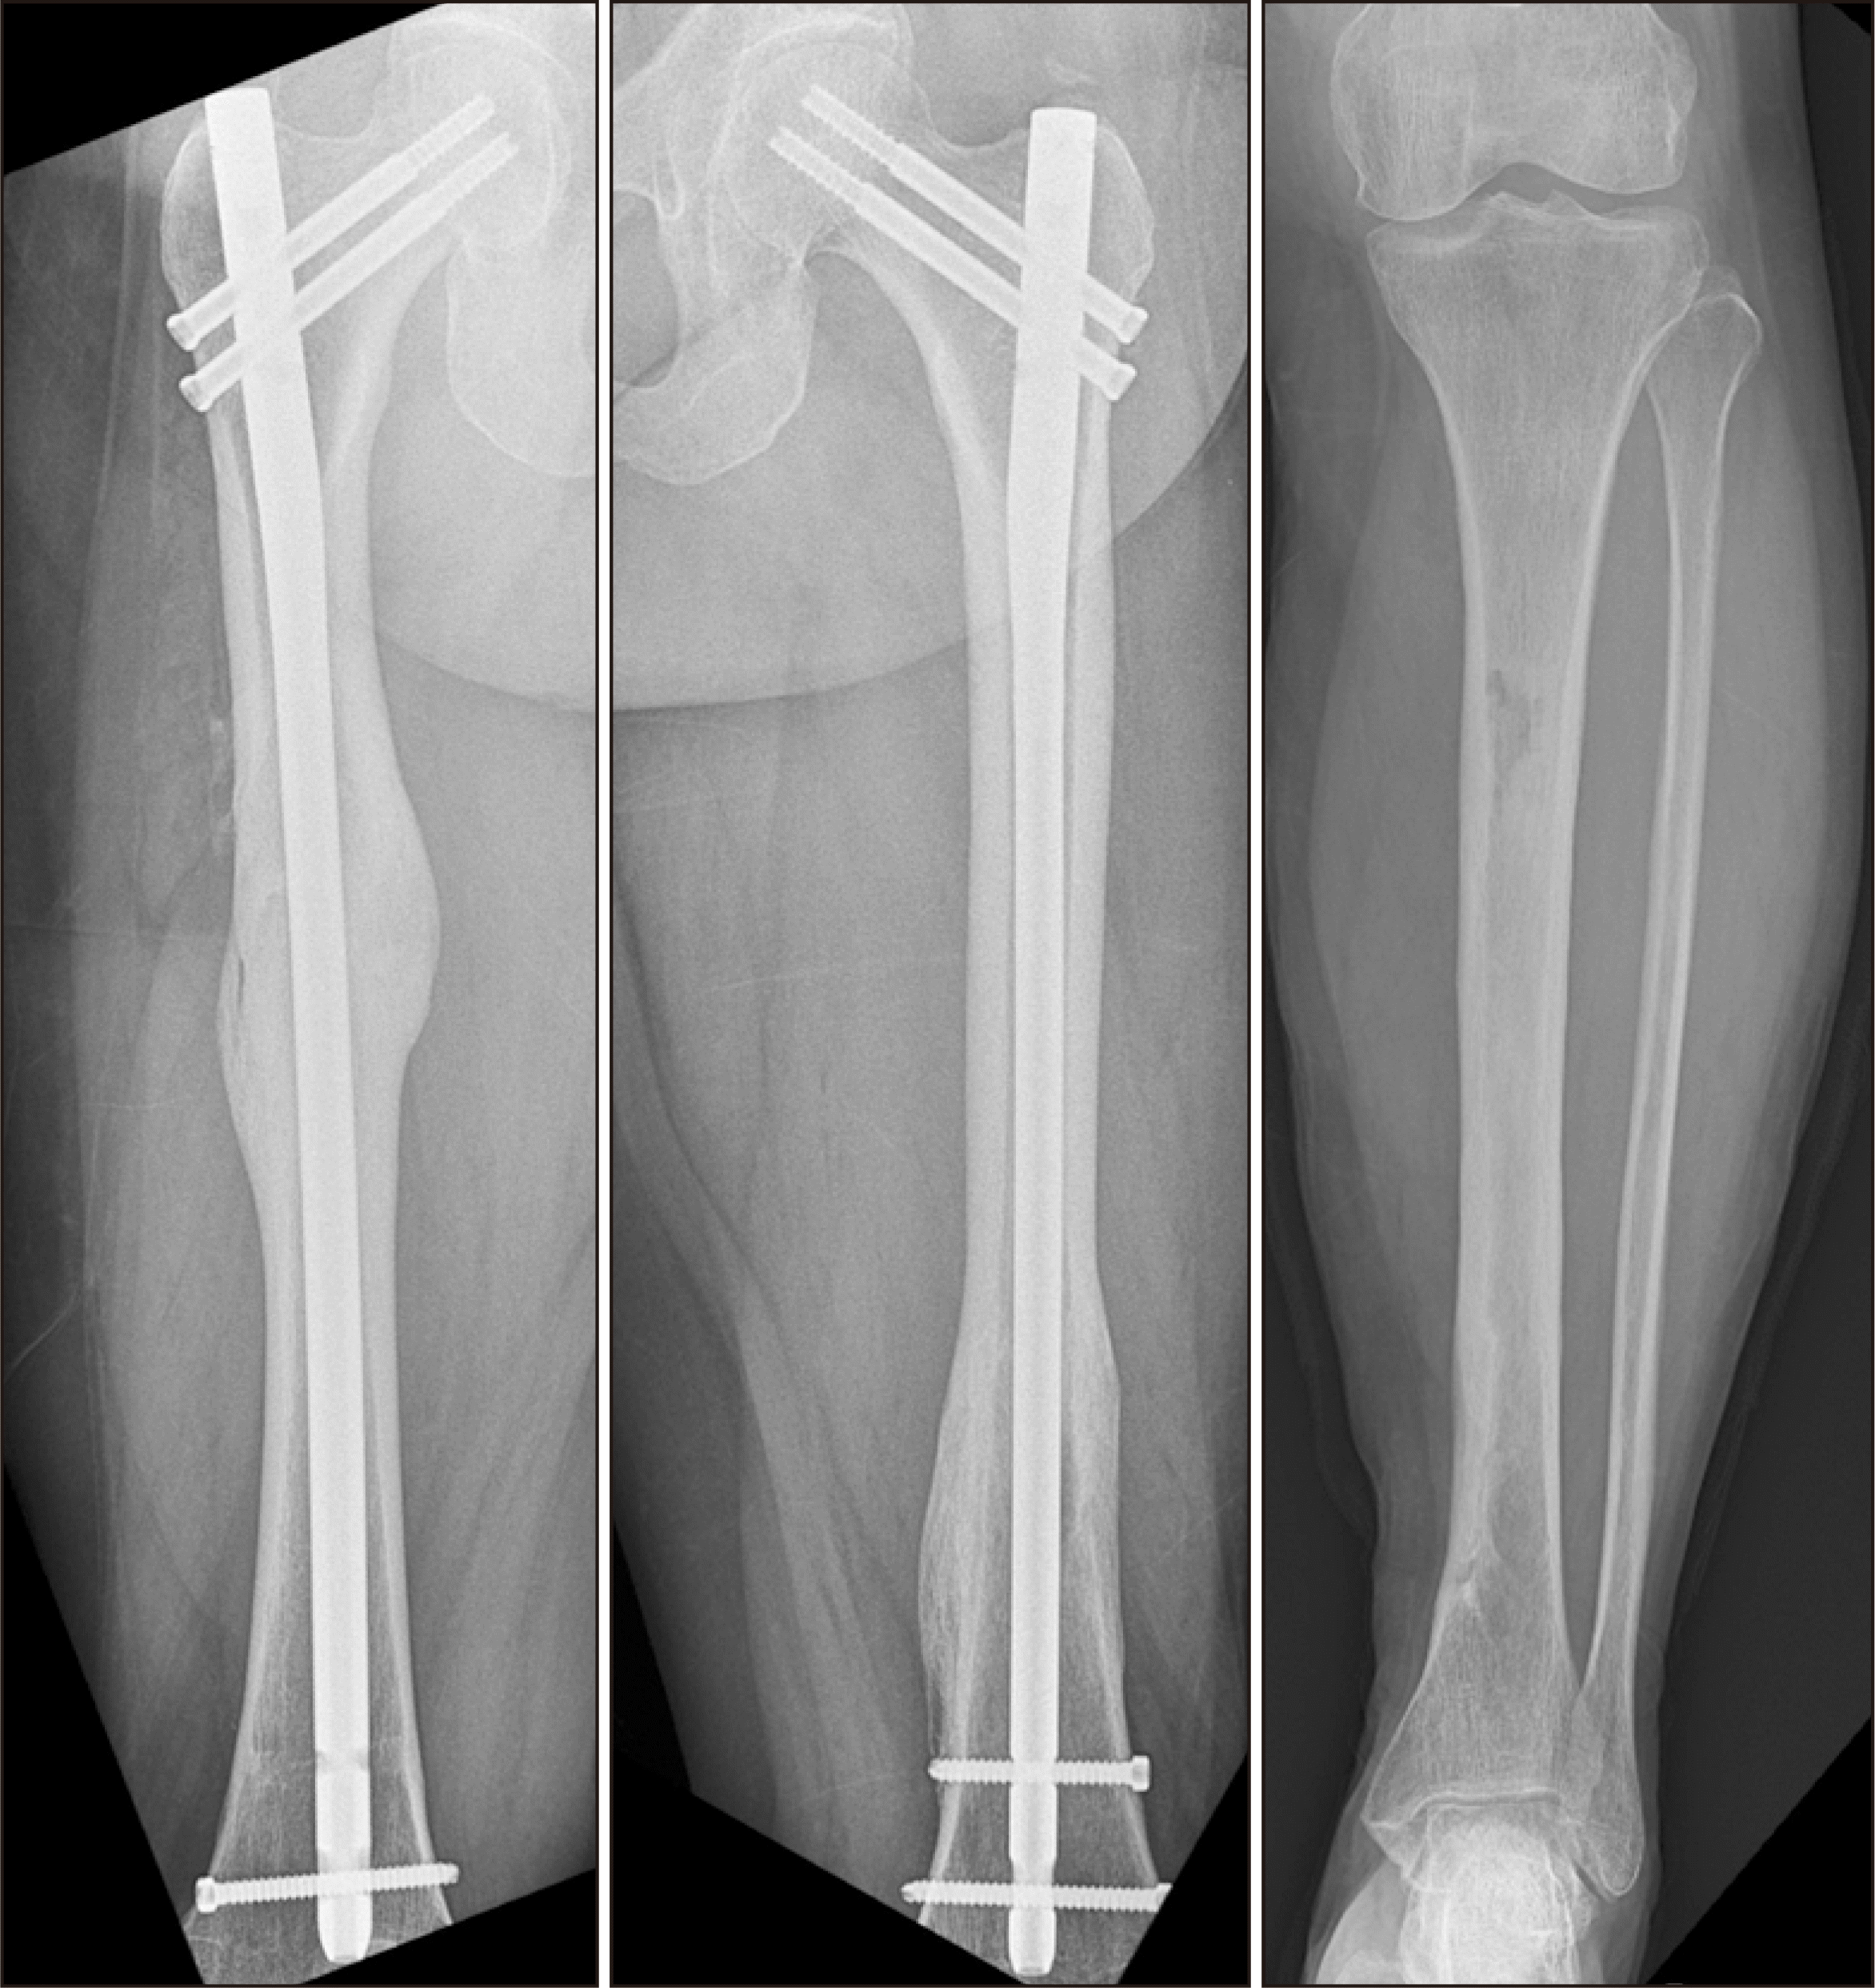

Figure 5

(A) The radiograph shows temporary circular wiring was done to minimize displacement of femur fracture after abscess drainage and curettage. After 1 week, intramedullary nailing was done. (B, C) The radiographs show osteolytic lesions in the lateral cortex of each tibia and distal femur. After abscess drainage with incision, bone curettage was done through the bone window, and antibiotic cement beads were inserted.